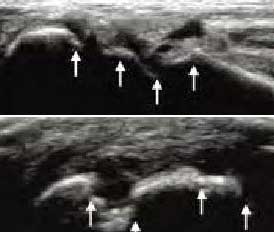

1、动态观察滑膜血流信号,早期监测RA活动

肌骨超声血流成像可清晰反映滑膜的血流情况,观测滑膜周边及内部异常血流信号的增多、血管翳增生程度,以及呈现出点状、星点状或枝状的不同形态,做到在RA的早期发现异常图像变化。通过对图像中血流信号的多少及区域范围进行评分,以此来辅助判断RA的活动程度。

超声对血流信号有超高的敏感性

• Ⅰ级血流

滑膜内异常血流信号:少量点状血流信号

• Ⅱ级血流

滑膜内异常血流信号:较多点状,短线状血流信号

• Ⅲ级血流

滑膜内异常血流信号:丰富的网状及树状血流信号